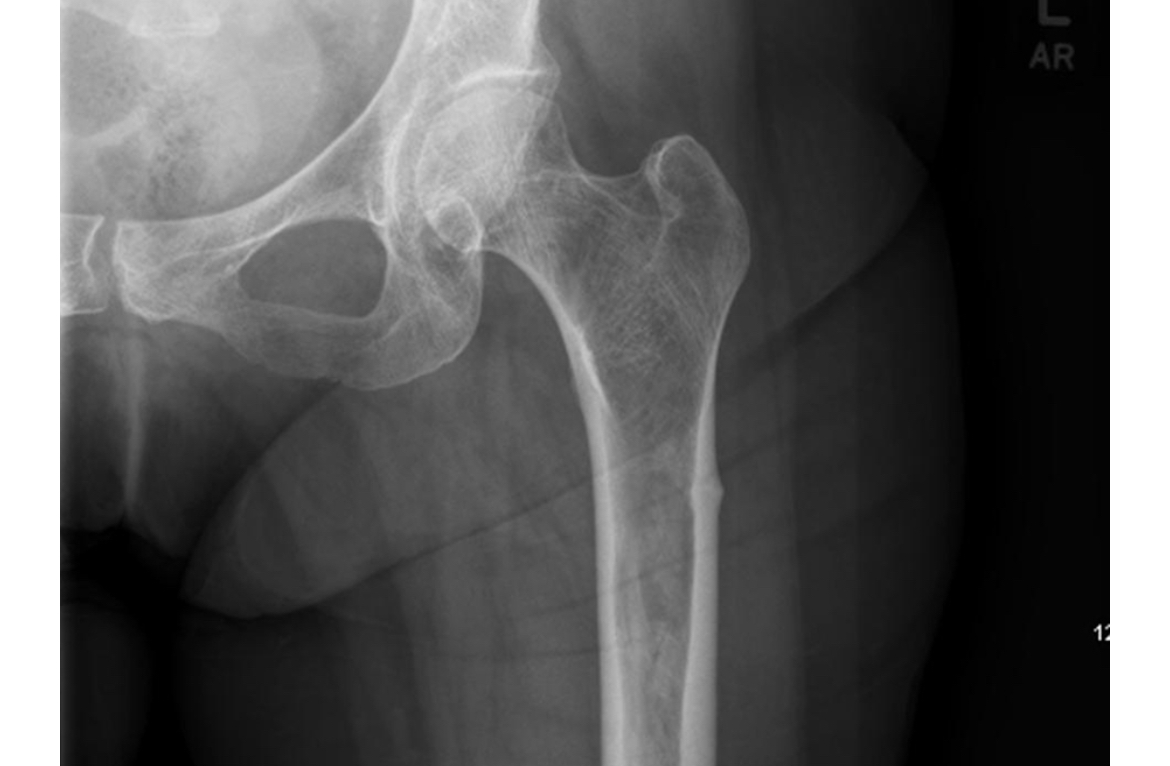

patient with joint pain and likely lung cancer, +Tx

Hypertrophic osteoarthropathy (HOA) is a syndrome characterized by digital clubbing, periostitis of long bones, and joint pain and swelling

can be primary or secondary (like this)

biopsy shows hypercellularity and vascular thickening

skin changes mimic acromegally

Tx celecoxib, then bisphosphonates